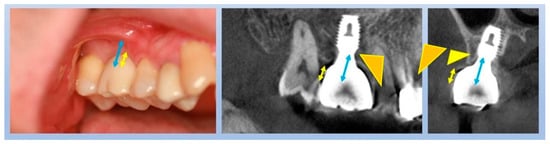

Figure 4 showcases a successful case of SPIs, demonstrating stable and esthetic outcomes. The clinical photos highlight natural soft tissue integration, while the CBCT images provide peri-implant soft tissue analysis, including measurements of transitional zone length (TZL) and soft tissue thickness (STT). These parameters help to evaluate the relationship between structural support and biological stability achieved with SPIs.

Figure 4.

Clinical and radiographic outcomes of an SPI-restored upper left first molar. Upper Two Images (Clinical Photos): Show the restored upper left first molar with well-integrated soft tissue, demonstrating a natural emergence profile and coronal flaring of the implant restoration. These features contribute to both biological stability and esthetic success. Lower Left Image (CBCT Cross-Section, Buccolingual View): Displays the implant placement. While the PCO effect suggests that the buccal margin is positioned more apically than the mesiodistal margin—resulting in a shorter overall distance from the fixture–abutment connection (FAC) to the soft tissue margin in the buccal aspect—this does not necessarily imply that the crestal zenith at the buccal side must always be positioned apically. Unlike the palatal side, where the crest may be observed at an epicrestal level, implant placement at the buccal side can still be subcrestal, provided it meets the required vertical depth for peri-implant stability or is intended to enhance the bone phenotype. Lower Right Image (CBCT with Measurements): Highlights the transitional zone length (TZL) and soft tissue thickness (STT), showing the vertical and horizontal dimensions of the peri-implant soft tissue. Additionally, it reflects the influence of the mesiodistal crestal slope (MDCS), emphasizing how ridge morphology affects implant positioning, peri-implant soft tissue stability, and overall emergence profile.